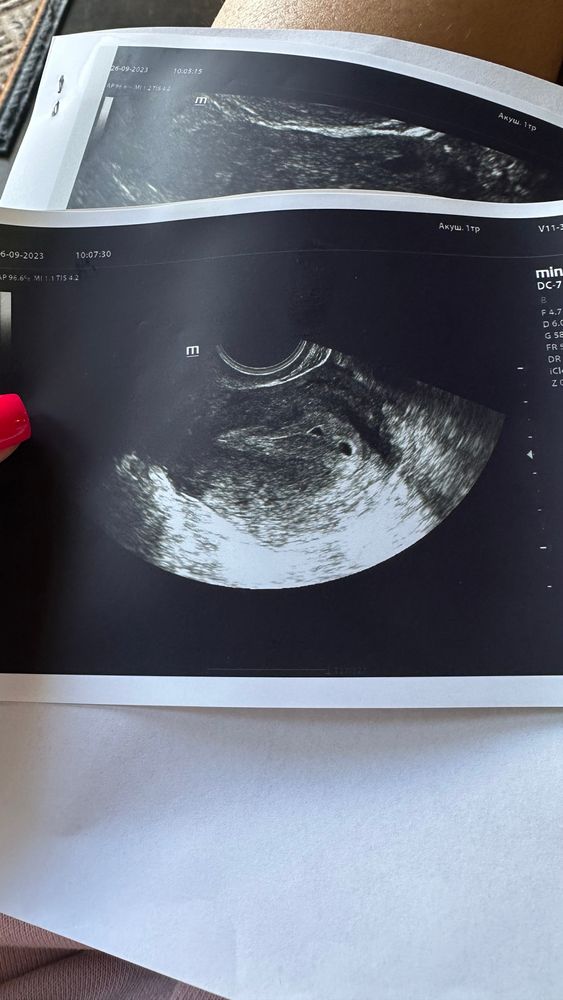

Nastasya , у меня ещё тоже хгч быстро растёт, сначала 84, а через 3 дня 617, то есть тоже в 7 раз вырос. Муж шутит, что двойня, а тут еще ваш пост😂

Nastasya , вот я дошутилась походу 😂 так что поосторожней там

Поздравляю вас, пусть детки держаться крепко! А на УЗИ было два доминантных фолликула? Интересно просто)

Rim Ka, нет, не говорили такого))) поэтому я вообще не ожидала. Хотя двойня еще не 100%, посмотрим через недельку ☺️

Кажется, у Вас и правда двойня 😍 поздравляю Вас от души 🤞🏻🍀

Мои две полосочки, я наконец-то их увидела 😍 Записалась на узи.